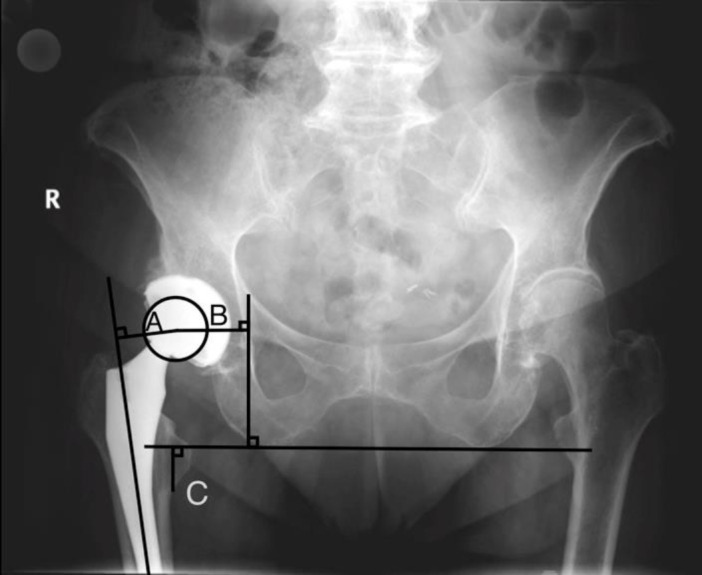

Methods: A retrospective case control study was developed from 542 patients who underwent primary THA over a 9-year period to form two patient cohorts. Two hundred and seventy-one patients diagnosed with LTP were matched with 271 controls. Chart review revealed patient demographics, surgical approach, and femoral components utilized. Change in limb length and offset were assessed through preoperative and postoperative radiographic measurements.

Results: There was a higher proportion of current or former smokers in the LTP group (34.5% vs 21.74%, p=0.003). There was no significant difference in use of high offset stems vs. standard offset stems between groups (15.9% vs. 18.5%, p=0.494). However, the LTP group had significantly higher increase in both femoral offset (+3.55mm vs +1.79mm, p<0.001) and total offset (+0.16mm vs -1.16mm, p=0.031) in comparison to controls.